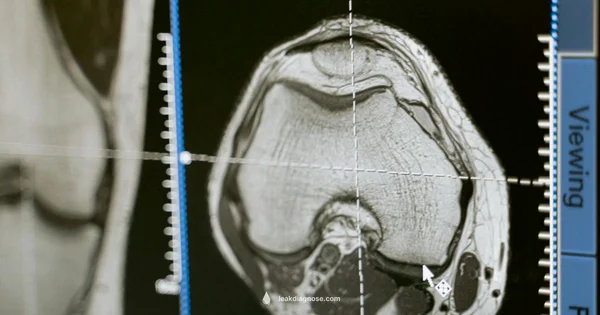

Diagnostic steps doctors use to confirm a CSF leak

Medical professionals use a combination of history, physical exams, and tests to confirm a CSF leak. A sample of the nasal drainage is analyzed for beta-2 transferrin, a highly specific CSF marker. Imaging studies, such as CT or MRI, help locate the tear and assess the skull base anatomy. In some cases, endoscopic nasal examination may reveal the source. The diagnosis may involve observing the drainage over time or triggering a Valsalva maneuver under supervision to see if the leak persists. Early and accurate diagnosis is important to prevent meningitis and plan treatment.